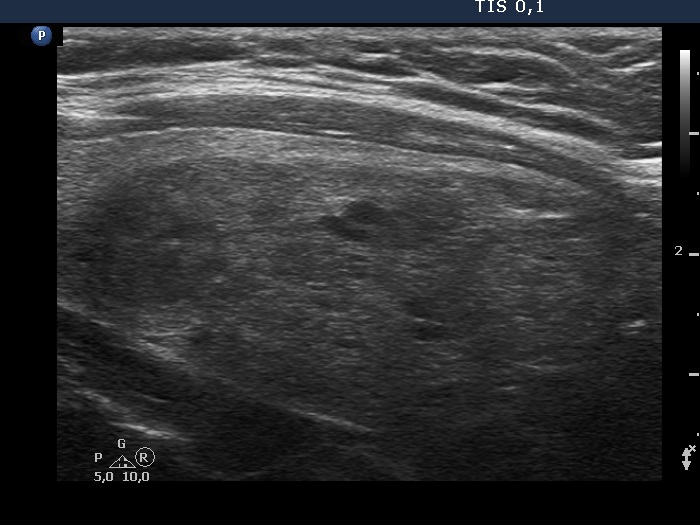

Study on 100 consecutive patients with thyroid nodule - case 067 (ultrasonographic picture 8)

Left lobe, another longitudinal view.